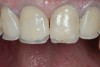

(2.) Preoperative retracted view.

Figure 2

A 34-year-old male patient with no medical issues presented to the office with the chief complaint of a failing crown on tooth No. 12. The patient was also unhappy with his bite and the appearance of his teeth (Figure 1 and Figure 2).

A comprehensive examination was carried out, and preoperative photographs were taken (Figure 1 through Figure 4). The patient presented with fair oral hygiene and slight, generalized tissue inflammation. Caries and defective restorations were detected on teeth Nos. 4, 5, 13, and 14. The crown on tooth No. 12 was showing signs of leakage, and although the endodontic access cavity had been temporarily restored with composite, this endodontic re-treatment was acceptable and the tooth was otherwise symptom-free. Erosion was present on most of the posterior teeth and the cuspids, and abrasion was noted on teeth Nos. 4, 5, 10, 11, 20, 21, 22, 28, and 29. An examination of the patient's muscles, joints, and bite revealed no joint sounds, a normal range of motion, and negative joint load and immobilization tests.

The dentofacial examination revealed a low smile line with no incisor display when the lips were in repose. The anterior teeth were chipped and worn, and their overall color was darkened. The buccal corridors were deficient, and the failing crown on tooth No. 12 was visible in a full smile.